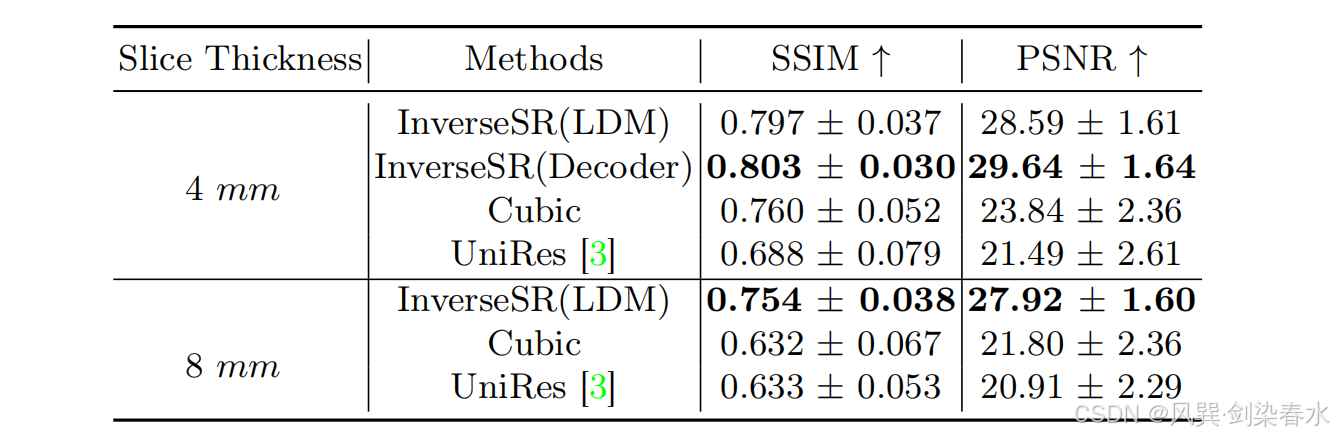

Table 1 | InverseSR 以及两个基线方法在 1 毫米扫描图像及其对应的超分辨率(SR)图像(分别从 4毫米 和 8毫米 轴向扫描图像生成)上的定量评估结果(均值 ± 标准误差):